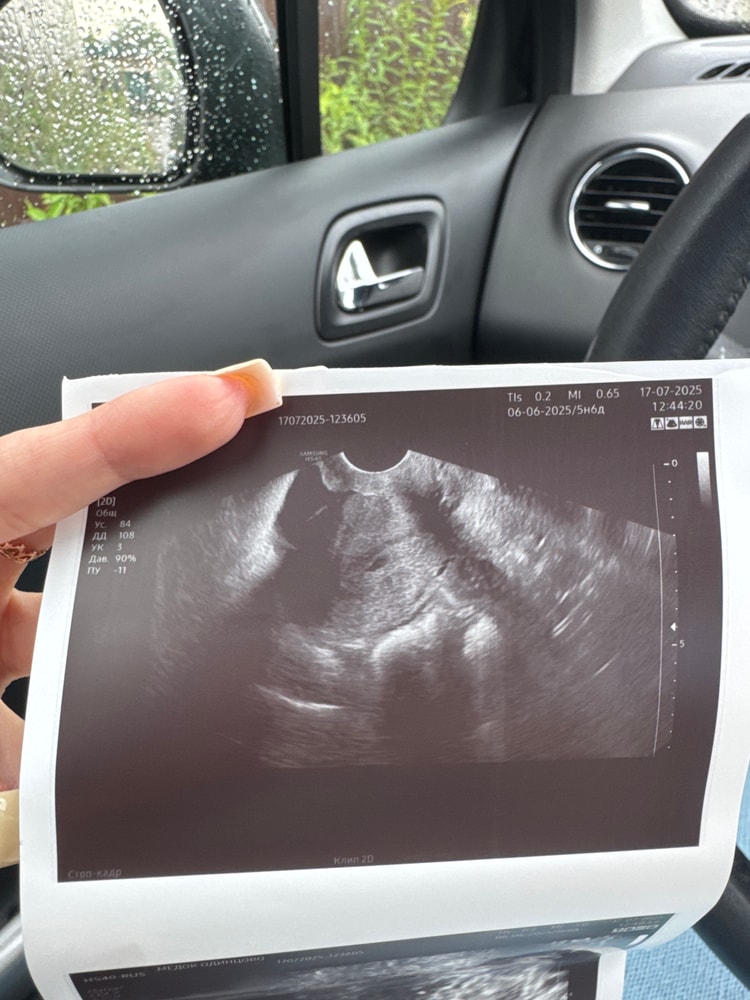

17.07.2025

Это совсем не похоже на плодное яйцо.

Раздвоение Птичности, сказали что похоже очень ,и желтое тело у меня и хороший эндометрий

Елизавета, сказали либо пя либо скопление жидскости